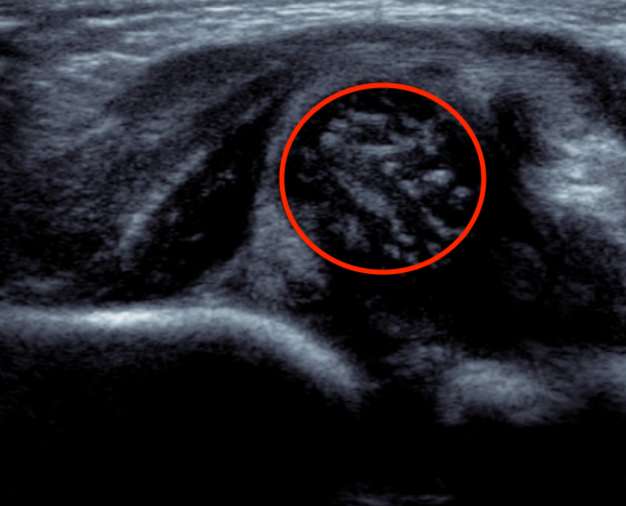

Dislocated hip on ultrasound